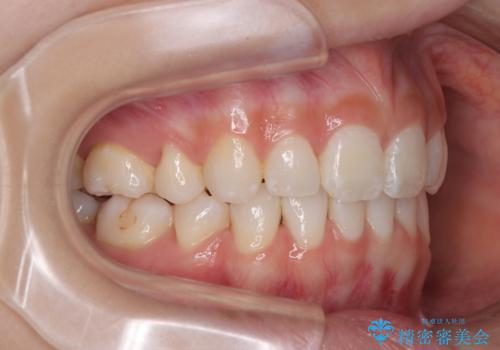

下唇に前歯が当たって跡が残ってしまう状態でしたが、スッキリとした口元に仕上げることができました。

下顎はデコボコが気になっていたため、上下左右第一小臼歯4本を抜去して、ワイヤー装置にて口元の突出感を改善するよう矯正治療を行うこととしました。